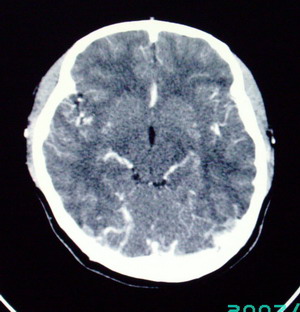

以下是引用九目段在2007-12-24 14:55:00的发言:[br]1,年轻女性[br]2,ct表现:左侧脑室三角区可见一不规则小明显强化的结节,中央见小低密度,侧脑室无扩张。[br]分析:[br]常见的有三种肿瘤好发三角区:[br]1,脉络丛乳头状瘤,好发于年轻者,明显强化,实性,分泌脑脊液,常伴有侧脑室扩大,肿瘤较小可以脑室扩大不明显,不能排除,但小结节尚不易形成坏死腔。[br]2,室管膜瘤,好发于儿童及青少年,明显强化,易坏死,大时伴脑室扩张。[br]3,脑膜瘤,明显强化,圆形,界请,无脑积水,一般不坏死。[br]诊断:[br]左侧脑室三角区结节,考虑室管膜瘤可能性大,不排除脉络丛乳头状瘤和脑膜瘤(因病史较长)。[br][br][本贴已被 九目段 于 2007-12-24 15:13:35 修改过]